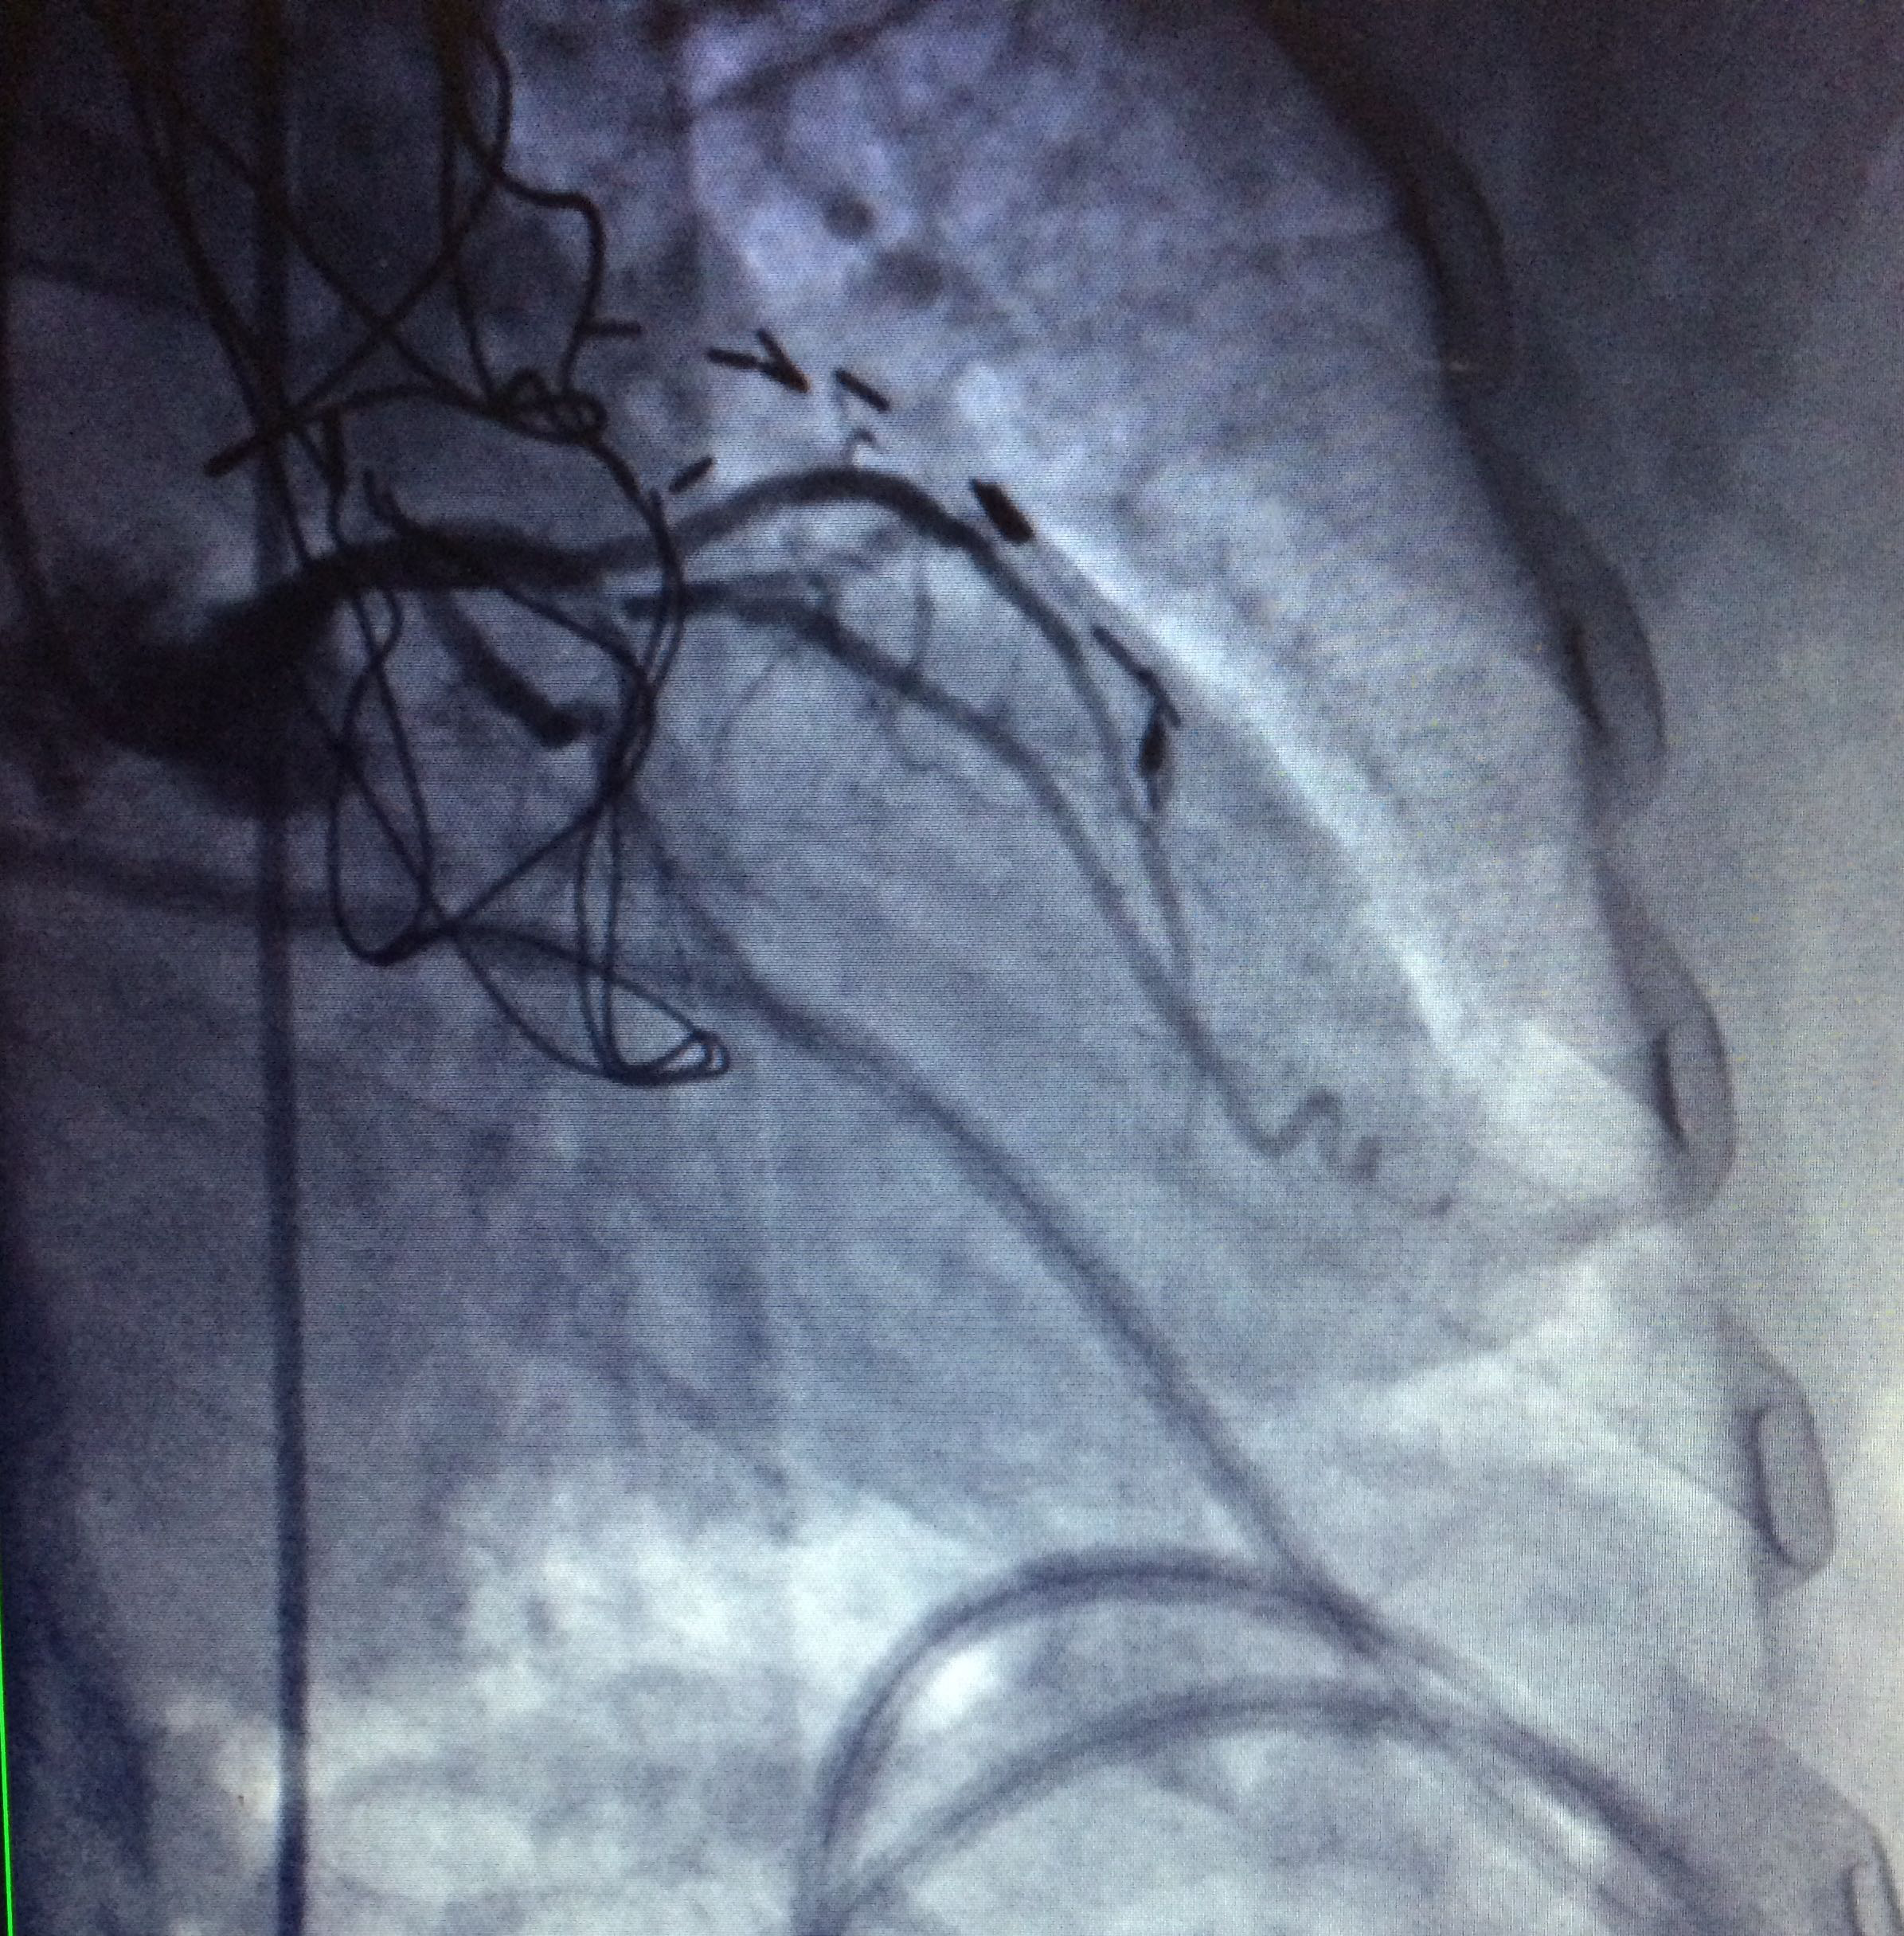

5. Right coronary artery with total occlusion at the proximal third (Figure 1-3).

Figure 1 Right coronary artery with total occlusion at the proximal third.

Figure 2 Right coronary artery with total occlusion at the proximal third.